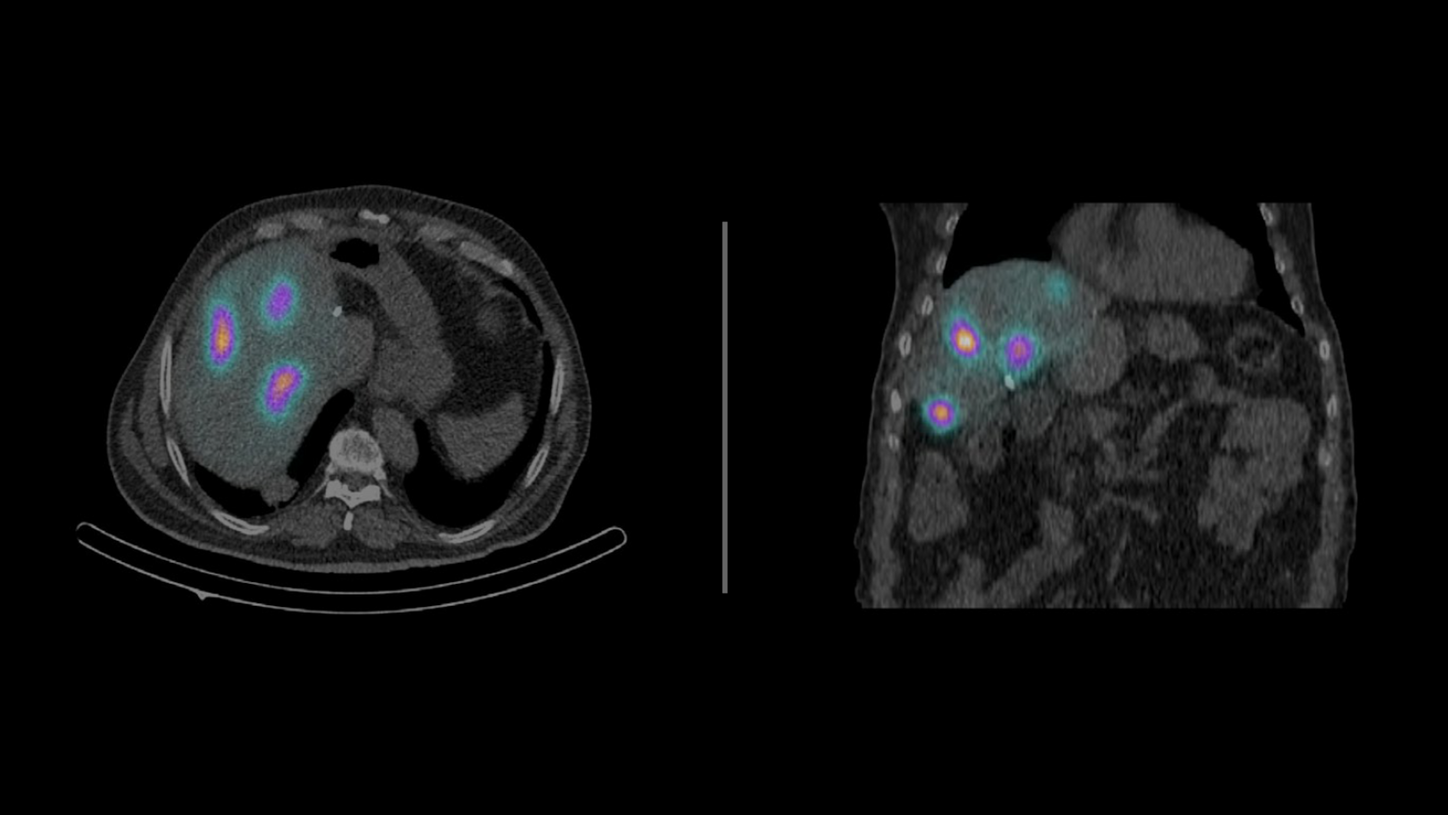

Transitioning to SPECT/CT accelerated the center鈥檚 evolution into a full-fledged theranostics hub. Today, nearly 50 percent of the department鈥檚 cancer patients are treated within theranostics pathways, including radioiodine therapy for thyroid cancer, lutetium-177 for prostate cancer (PSMA therapy) and neuroendocrine tumors (peptide receptor radionuclide therapy), and radioembolization.听

鈥淭he combination of SPECT/CT and personalized dosimetry is critical to providing optimal outcomes in theranostics,鈥 says Koutsikos. 鈥淨uantitative imaging, low-dose diagnostic CT, and improved tumor localization are essential for both patient safety and therapeutic success.鈥澨

Throughout the theranostics process, patients often undergo multiple scans鈥攂efore and after treatment cycles鈥攖o monitor therapeutic uptake and assess effectiveness. This valuable imaging during treatment is one of the great advantages of theranostics, offering clinicians real-time insight into how well a treatment is working. However, it also raises concern about cumulative radiation exposure, particularly for patients undergoing long-term therapies.

Considering these concerns, a critical component of theranostics is dosimetry, the measurement of the absorbed radiation dose in tissues, which helps optimize treatment planning and ensure patient safety. While the dosimetry of radionuclide therapy is important to protect sensitive organs, another measure to reduce exposure is utilization of low-dose CT in subsequent scanning protocols.